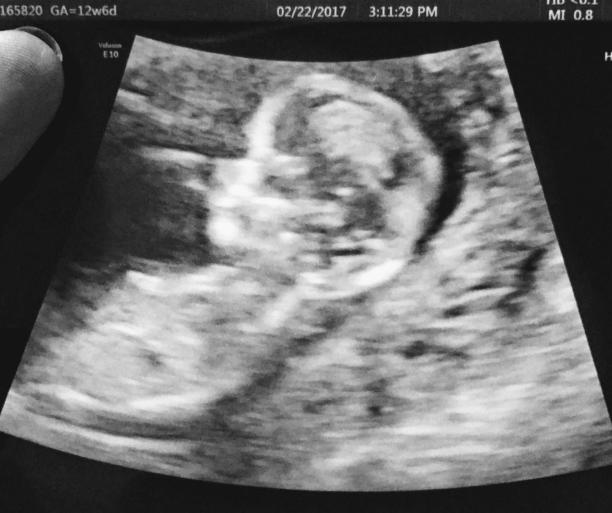

Las palabras del doctor me tranquilizaron porque yo realmente sentía que iba a tener un “Alien” porque a uno le dicen tantas cosas que el miedo no te deja pensar. En esta cita me hicieron mi tercer eco, donde pude realmente ver a mi bebé por primera vez más formadito. En este eco es cuando le miden la nuca al bebé y pueden detectar si el bebe tiene sindrome de down u otros problemas genéticos. Gracias a Dios todo salió bien. Por mi edad tambien me hicieron un examen genético que se llama Panorama por medio de la sangre, ya que en la sangre llevas el DNA del bebé también. Este examen detecta anomalías cromosómicas y también te detecta el sexo del bebé si lo quieres saber.